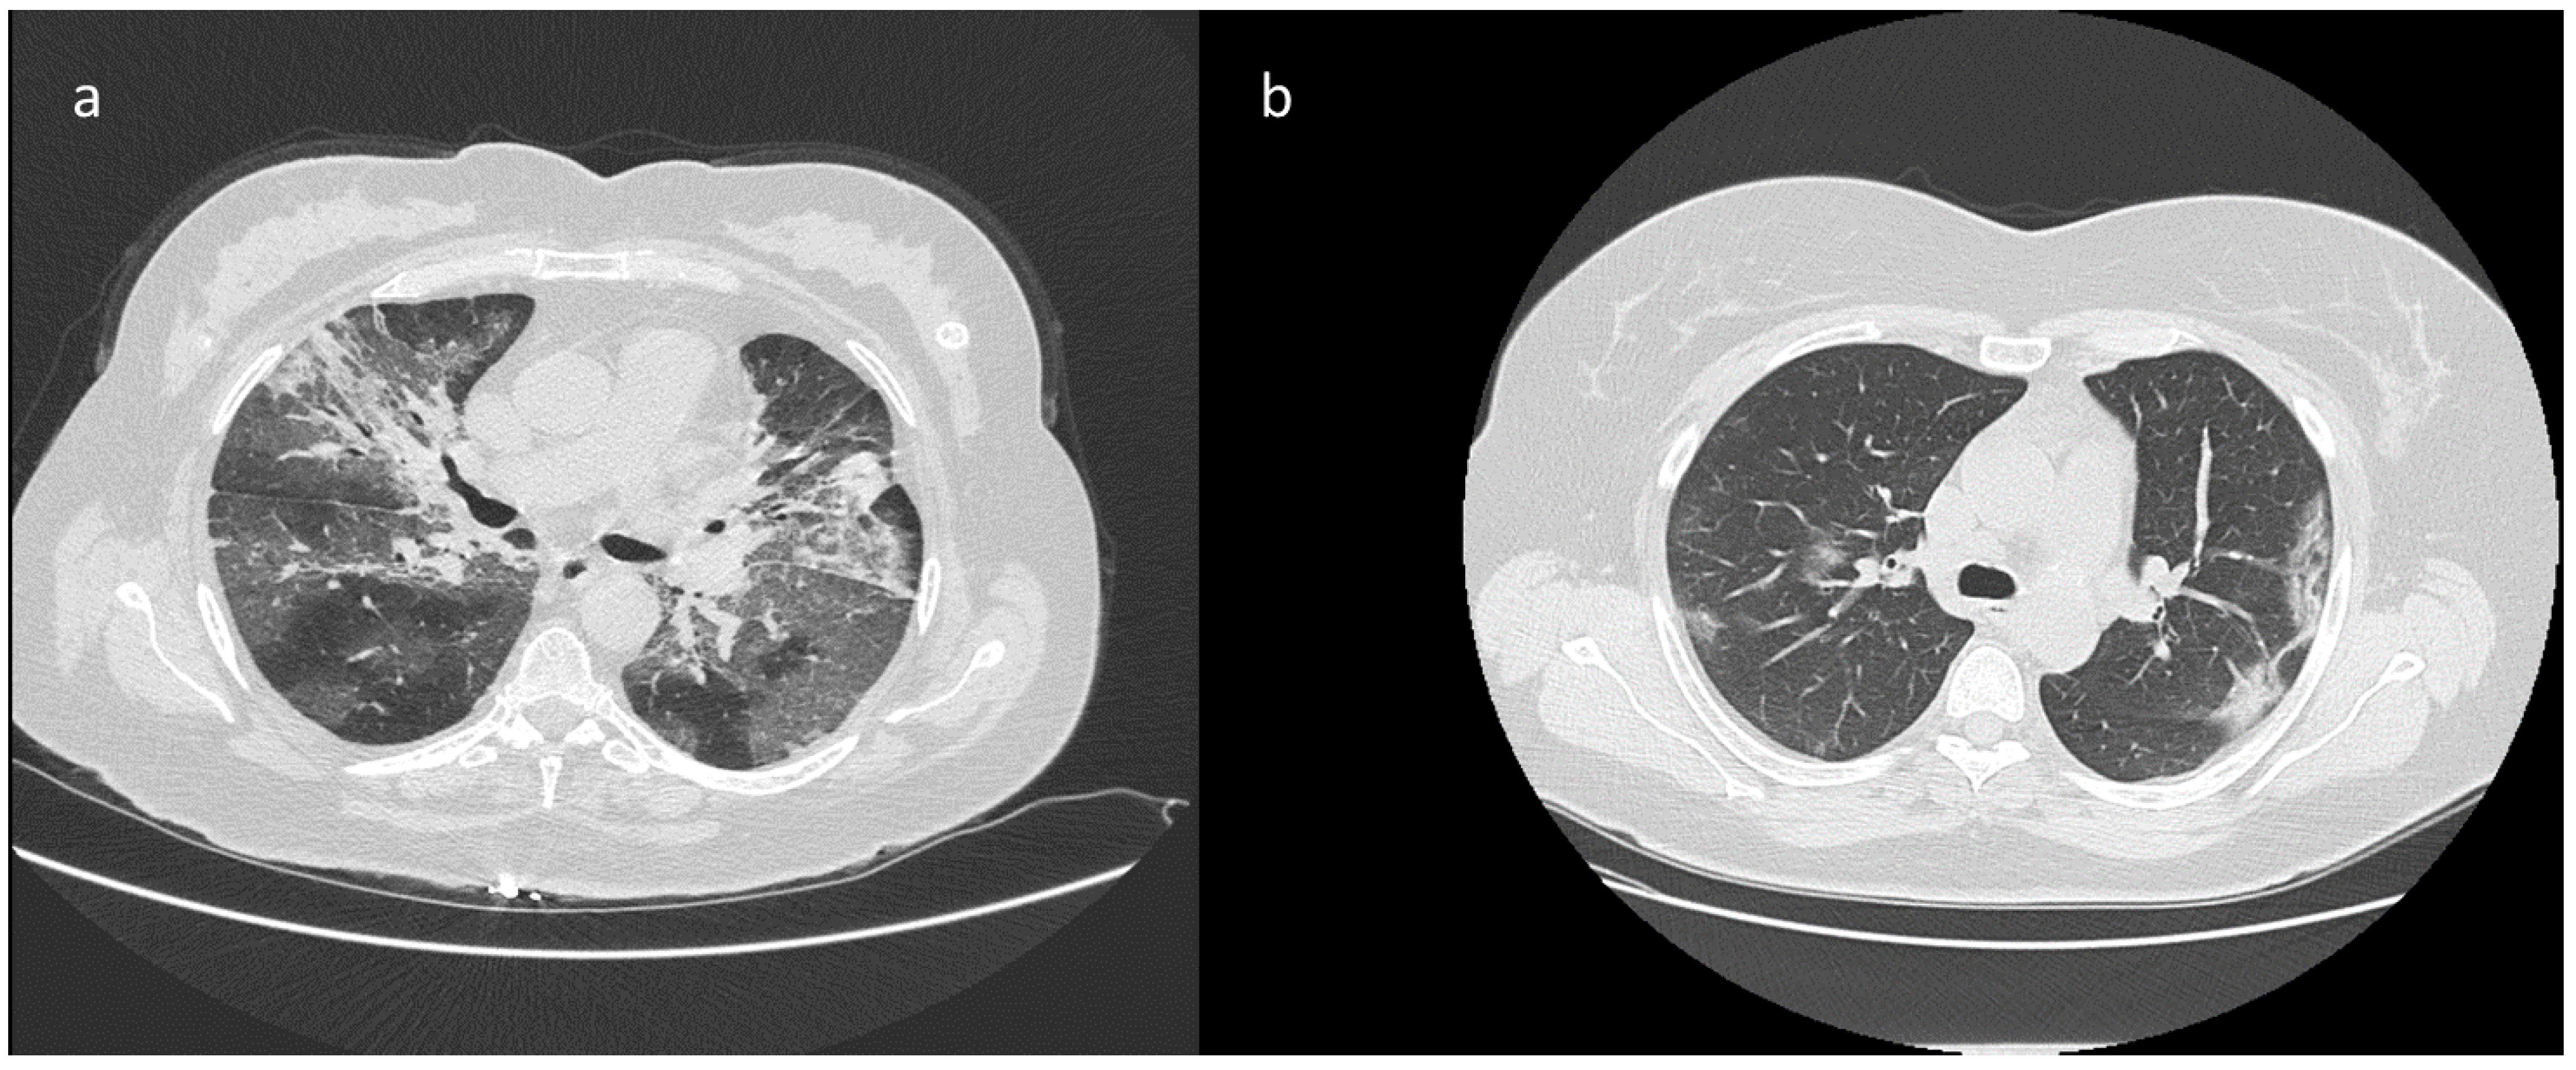

| High diagnostic confidence level | Bilateral multifocal GGO with predominantly peripheral distribution associated or not with septal thickening (crazy paving) and/or consolidations; multifocal GGO of rounded morphology associated or not with crazy paving and/or consolidations; multifocal GGO associated with findings of organizing pneumonia. |

| Intermediate diagnostic confidence level | GGO with diffuse distribution associated or not with crazy paving and/or consolidations; bilateral multifocal GGO and/or consolidations without a prevalent peripheral distribution and without rounded morphology; unilateral GGO with or without consolidation. |

| Low diagnostic confidence level | Isolated small areas of GGO and/or consolidations with non-rounded morphology were included in the low confidence level. |

| Negative for COVID-19 | Cases without the described alterations and with one or more of the following alterations were considered indicative of other diagnoses: isolated lobar or segmental consolidations, presence of solid or caveated nodules, presence of micro-nodules (centro-lobular micro-nodules and “tree in bud” pattern), smooth thickening of the interlobular septa with pleural effusion. |